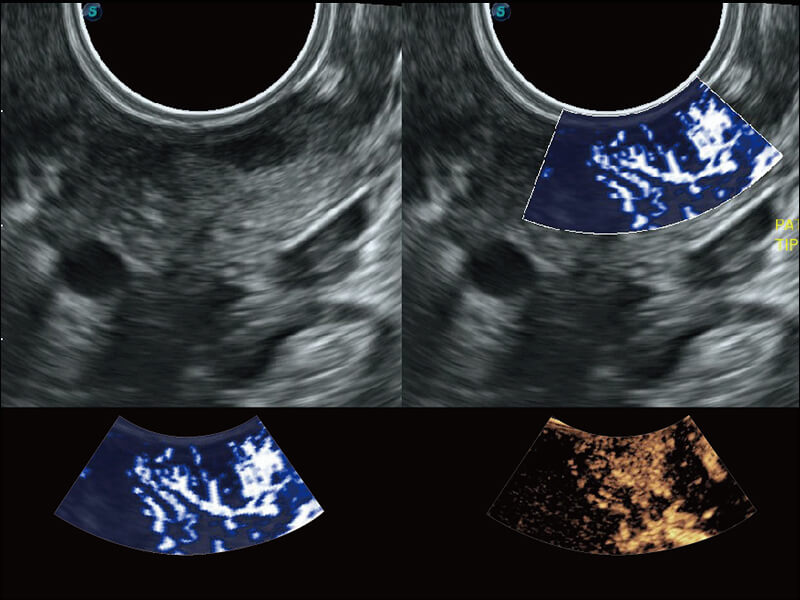

Micro F 显微血流成像 明察秋毫